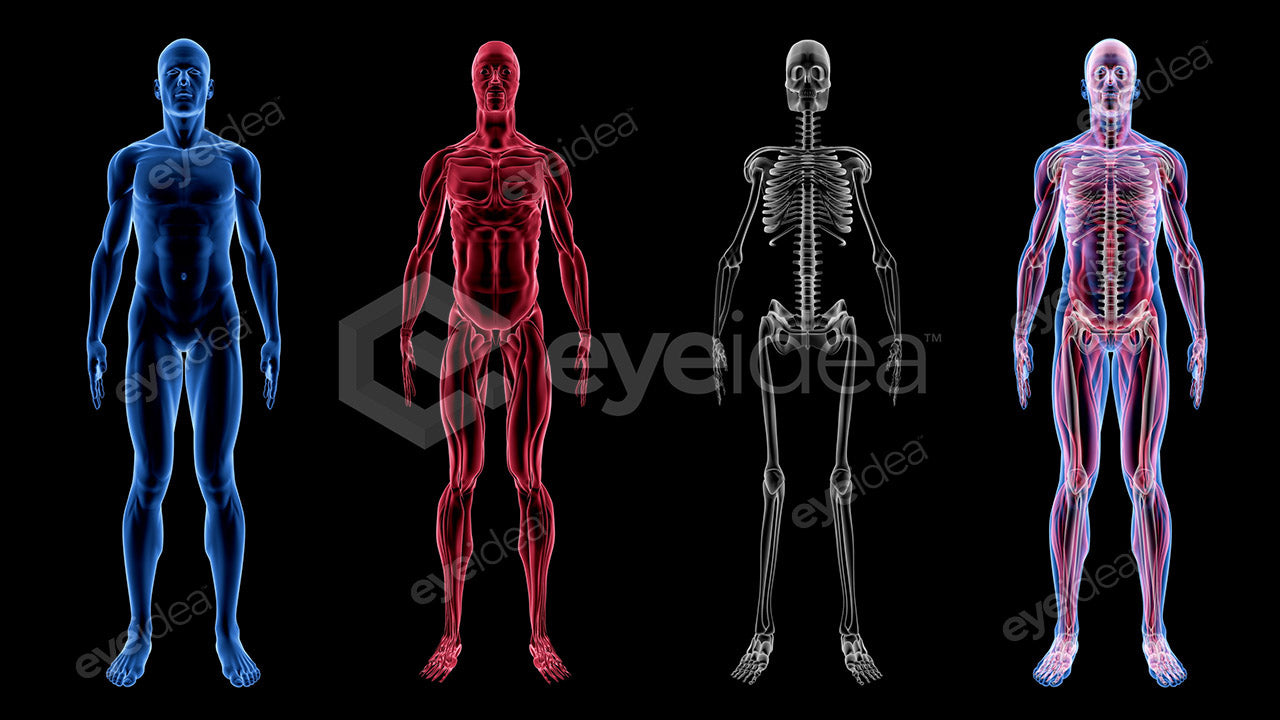

Versatility and Variety

Our Stock-Packs™ are curated to include a varied

range of angles, motion, styles and formats,

ensuring that creators can find the assets

they want fast and easy.